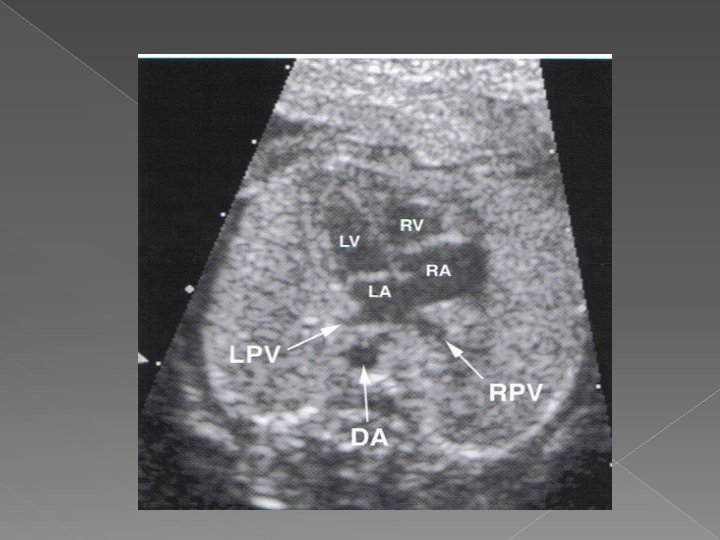

� Heart › A 4 chamber view should be visualized › Includes the RA, LA, RV, and LV › The rt. & lt. pulmonary vein, descending aorta, and lungs may also be visualized

Four chamber view › The 4 cv is the single most important image of the fetal heart. › Normal features are: �Apex of heart points 45 degrees to left anterior chest wall �Ventricles approx. the same size (right can be larger than left in pregnancy) �Flap of foramen of ovale opens into left atrium �Prominent moderator bands present in apex of right ventricle �Valves separate both atria from ventricles

The normal 4 -chamber view

� Normal orientation of the 4 chamber heart view within the fetal chest: the heart should take up 1/3 of the chest cavity with the apex pointing to the left chest wall.